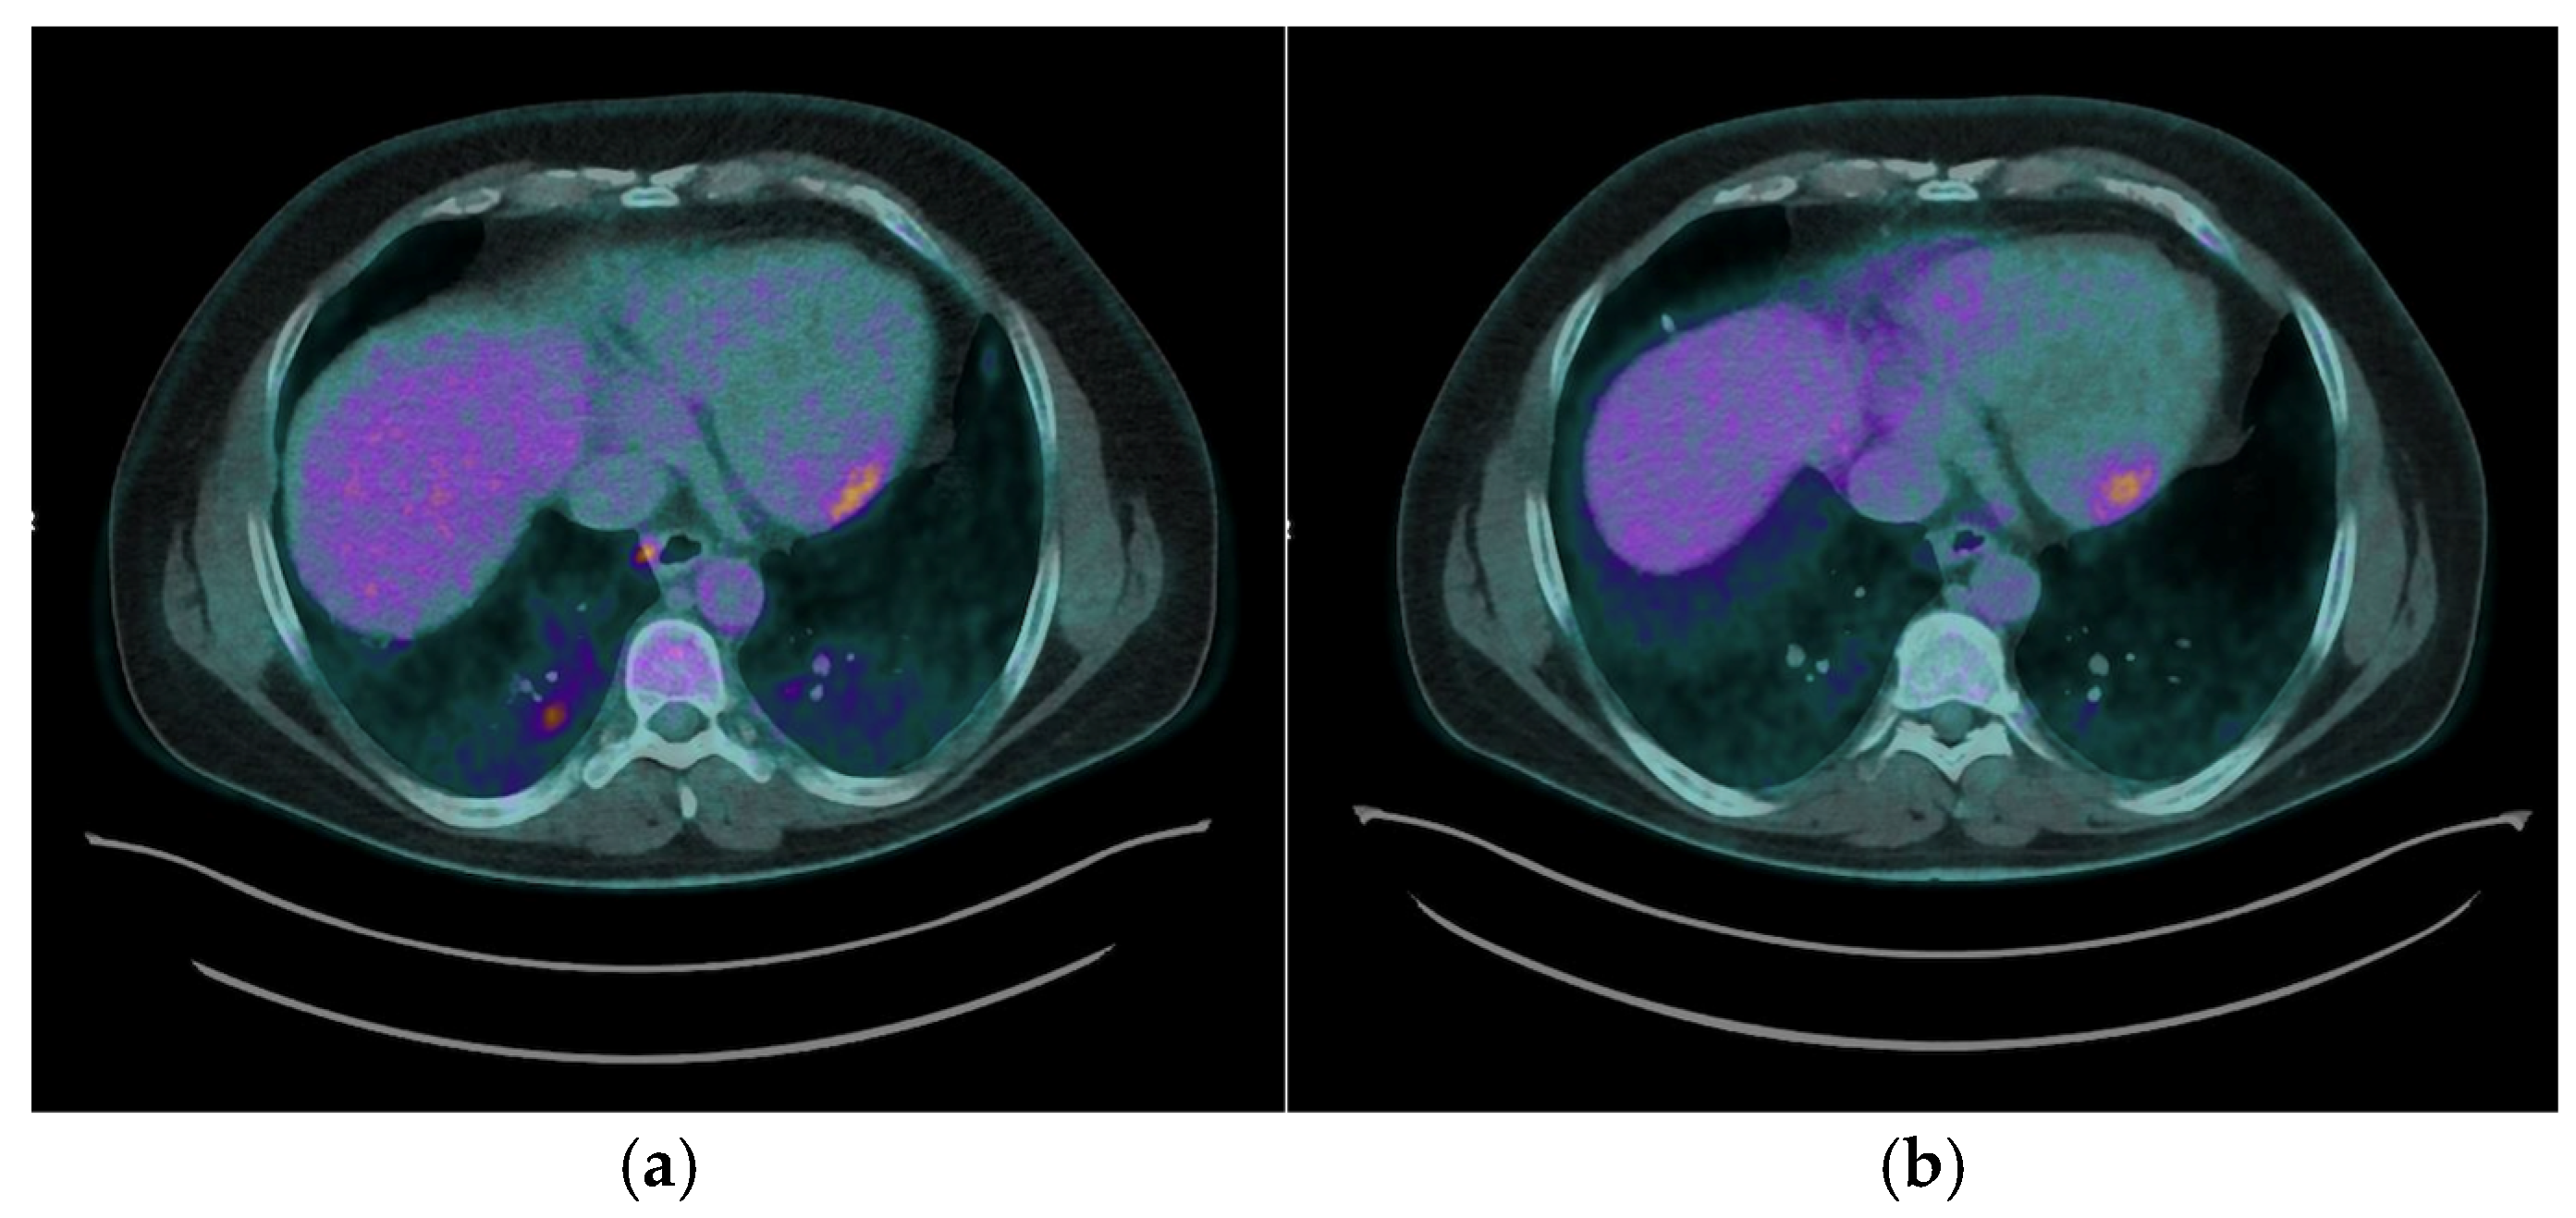

- The integration of perfusion imaging with 13N-NH3 PET/CT enhances the diagnostic and prognostic value of PET/CT. By distinguishing areas of perfusion defects (indicative of fibrosis) from regions of increased FDG uptake (active inflammation), clinicians can fully characterize the spectrum of disease, from isolated inflammation to fibrosis, and overlapping pathology, for comprehensive disease evaluation, prognosis, and guiding tailored therapeutic strategies [9].

- Cardiac magnetic resonance (CMR) imaging is the first-line advanced diagnostic test for CS; however, it was not feasible for all patients and sometimes produced inconclusive results, further illustrating the diagnostic gap that PET/CT can address. In this regard, our findings confirm that FDG PET/CT is highly sensitive for detecting active myocardial inflammation, as demonstrated by the characteristic uptake patterns observed.

- Moreover, our findings reinforce the utility of PET/CT in guiding individualized treatment strategies. By offering a non-invasive assessment of myocardial inflammatory activity, PET/CT allows clinicians to tailor immunosuppressive therapy based on objective evidence of disease activity or remission. This approach facilitates the adjustment of immunosuppressive regimens, such as corticosteroids and steroid-sparing agents, while minimizing unnecessary exposure to medication side effects, thereby improving patient safety and quality of life [13]. Serial PET/CT imaging enhances disease monitoring by enabling quantitative and qualitative assessments of therapeutic response. In our cohort, follow-up PET/CT scans confirmed a complete metabolic response in most patients (77.8%), supporting decisions to taper immunosuppressive therapy in selected cases (25%). Conversely, persistent or recurrent FDG uptake necessitated continued or intensified treatment (75%), underscoring the role of PET/CT in dynamic, patient-centered clinical management.